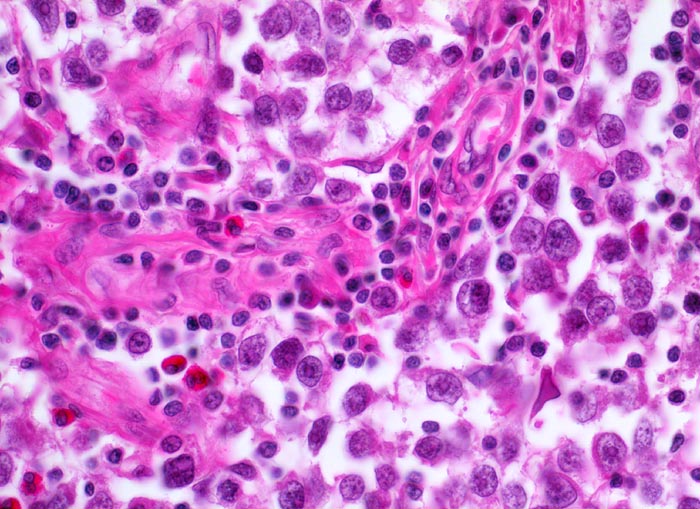

Seminom des Hodens

Aufgrund der suboptimalen Fixation sind die Tumorzellen diskohäsiv und das Zytoplasma ist geschrumpft. Die Tumorzellen haben grosse hyperchromatische Kerne mit einem typischen grossen zentralständigen eosinophilen solitären Nukleoli. Ebenfalls typisch das begleitende überwiegend lymphozytäre Entzündungsinfiltrat und einzelne eosinophile Granulozyten.

Makroskopisch aus mehreren Knoten bestehender weisser Tumor von 2cm Durchmesser.

Der Patient suchte den Arzt wegen einer schmerzlosen Hodenvergrösserung auf.

Histologie

400